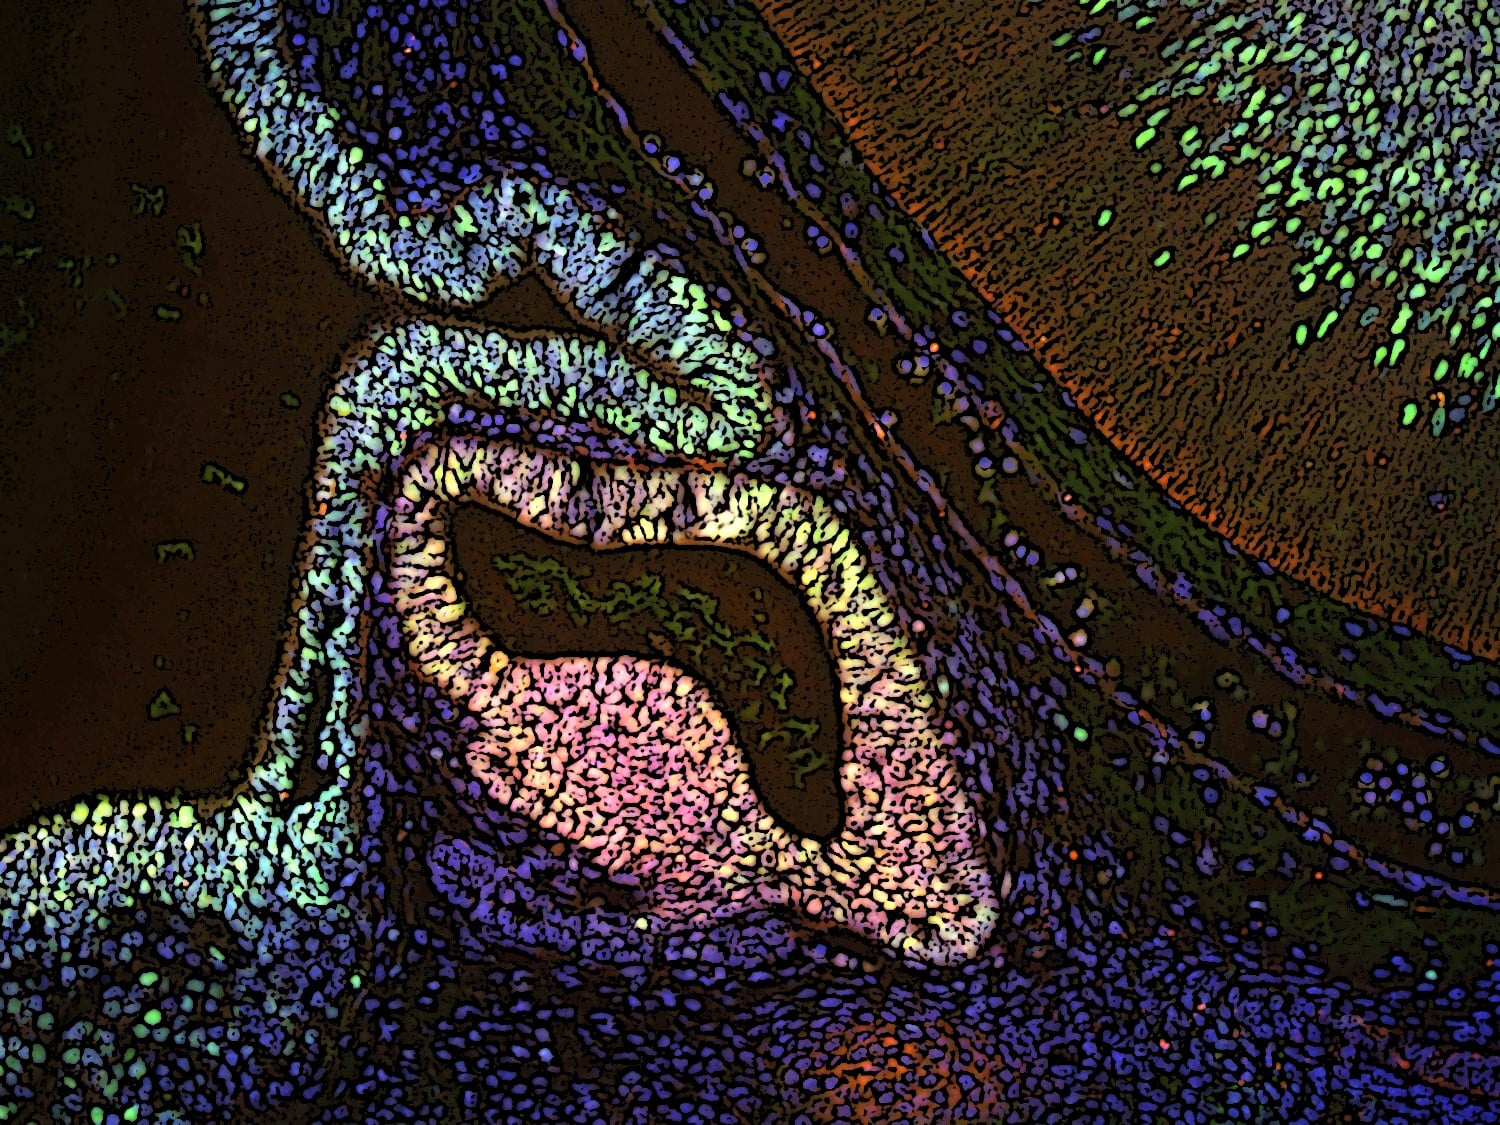

Drayson Jaffee, Anthony Yin, Ian Jaffee – California Pacific Medical Center

Metastatic medullary thyroid carcinoma to the liver: The original image was a 400X hematoxylin and eosin (H&E) stained slide for conventional light microscopy documenting pathology confirmation of metastatic medullary thyroid carcinoma to the liver. The image was subsequently modified with solarizing effect and central ballooning expansion of the neoplastic deposit. Peritumoral endothelialized capillaries are enhanced by aqua staining; and erythrocytes are further delineated by magenta staining, capturing the inherent capacity for these rare malignancies to characteristically disseminate via the peripheral vascular system.